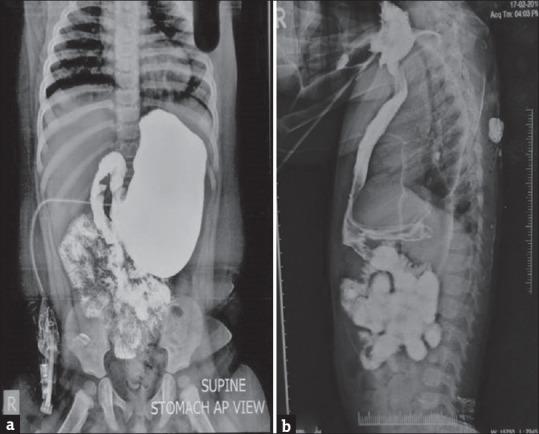

This study, spanning 10 years (January 2012 to January 2022), focused on pure EA and LGEA with TEF. The three-stage approach included neonatal gastrostomy and esophagostomy, the creation of an isoperistaltic gastric tube at around 10 kg body weight, retrosternal tunneling, and subsequent closure of the cervical esophagostomy. Data on gender, weight, age, complications, gastric emptying, esophageal mucosal status, gastroesophageal reflux, and growth and nutritional status were analyzed.

本研究历时10年(2012年1月至2022年1月),聚焦于单纯EA和伴有TEF的LGEA。三阶段方法包括新生儿胃造口术和食管造口术,在体重约10kg时制作等蠕动胃管,胸骨后隧道形成,以及随后关闭颈部食管造口。分析了性别、体重、年龄、并发症、胃排空、食管黏膜状况、胃食管反流以及生长和营养状况的数据。